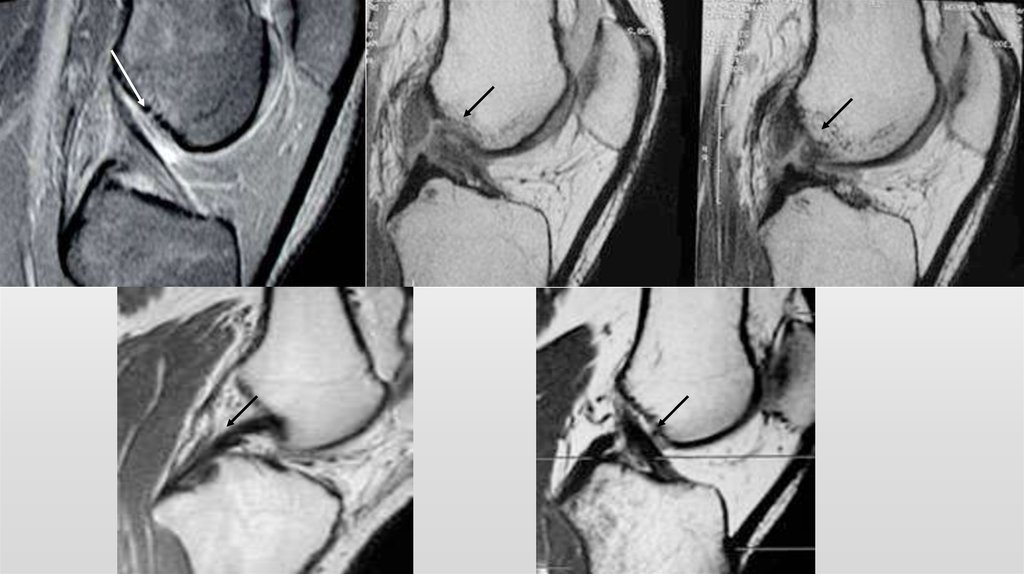

2. ПОВРЕЖДЕНИЯ КРЕСТООБРАЗНЫХ СВЯЗОК

8. Открытое подшивание и пластика

9.